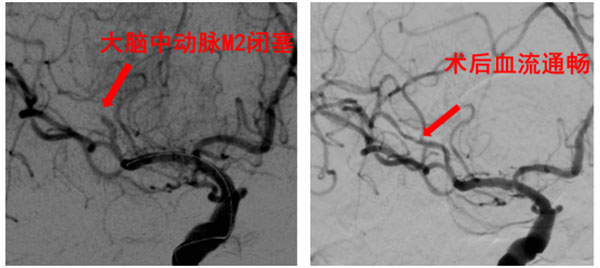

病例3——睡醒后的突然偏瘫:(79岁男性)患者睡醒后自觉左侧肢体无力、言语不清,由家属急送入院。检查提示右侧大脑中动脉分支闭塞,供血区大面积低灌注。急诊取栓术后,大脑中动脉成功再通,为后续康复创造了条件。